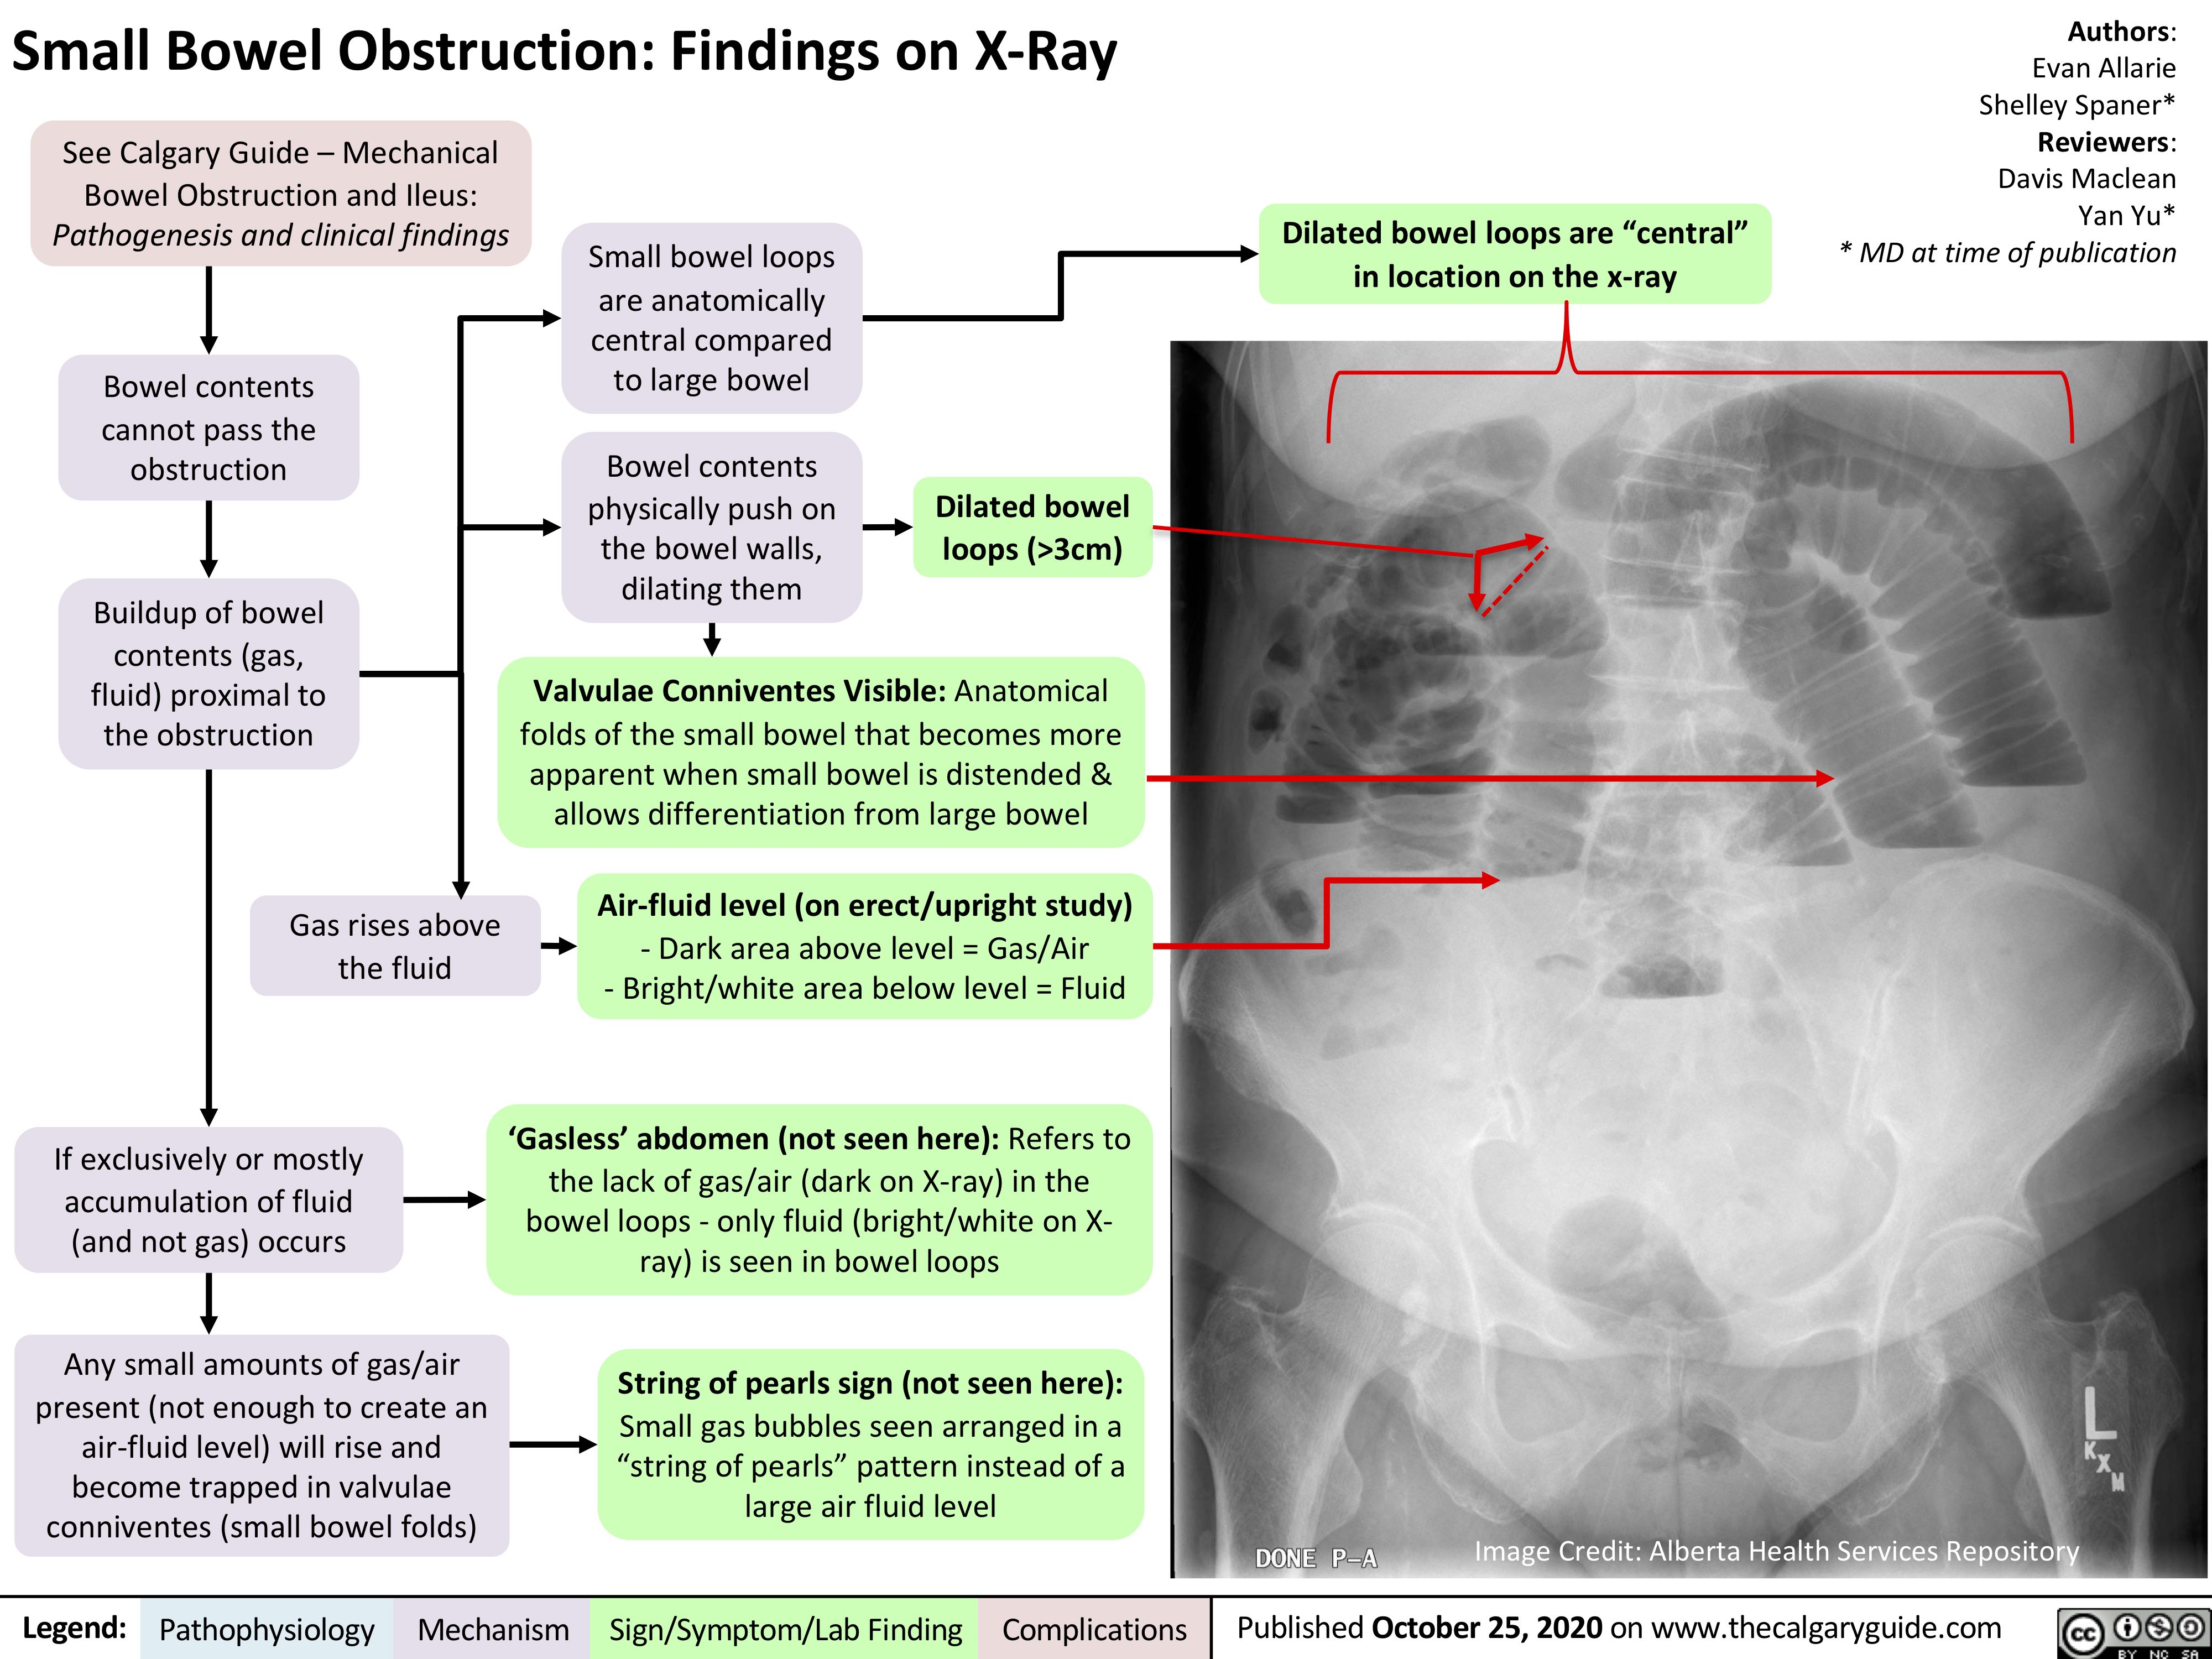

Small Bowel Obstruction Findings On X Ray Calgary Guide

Small Bowel Obstruction